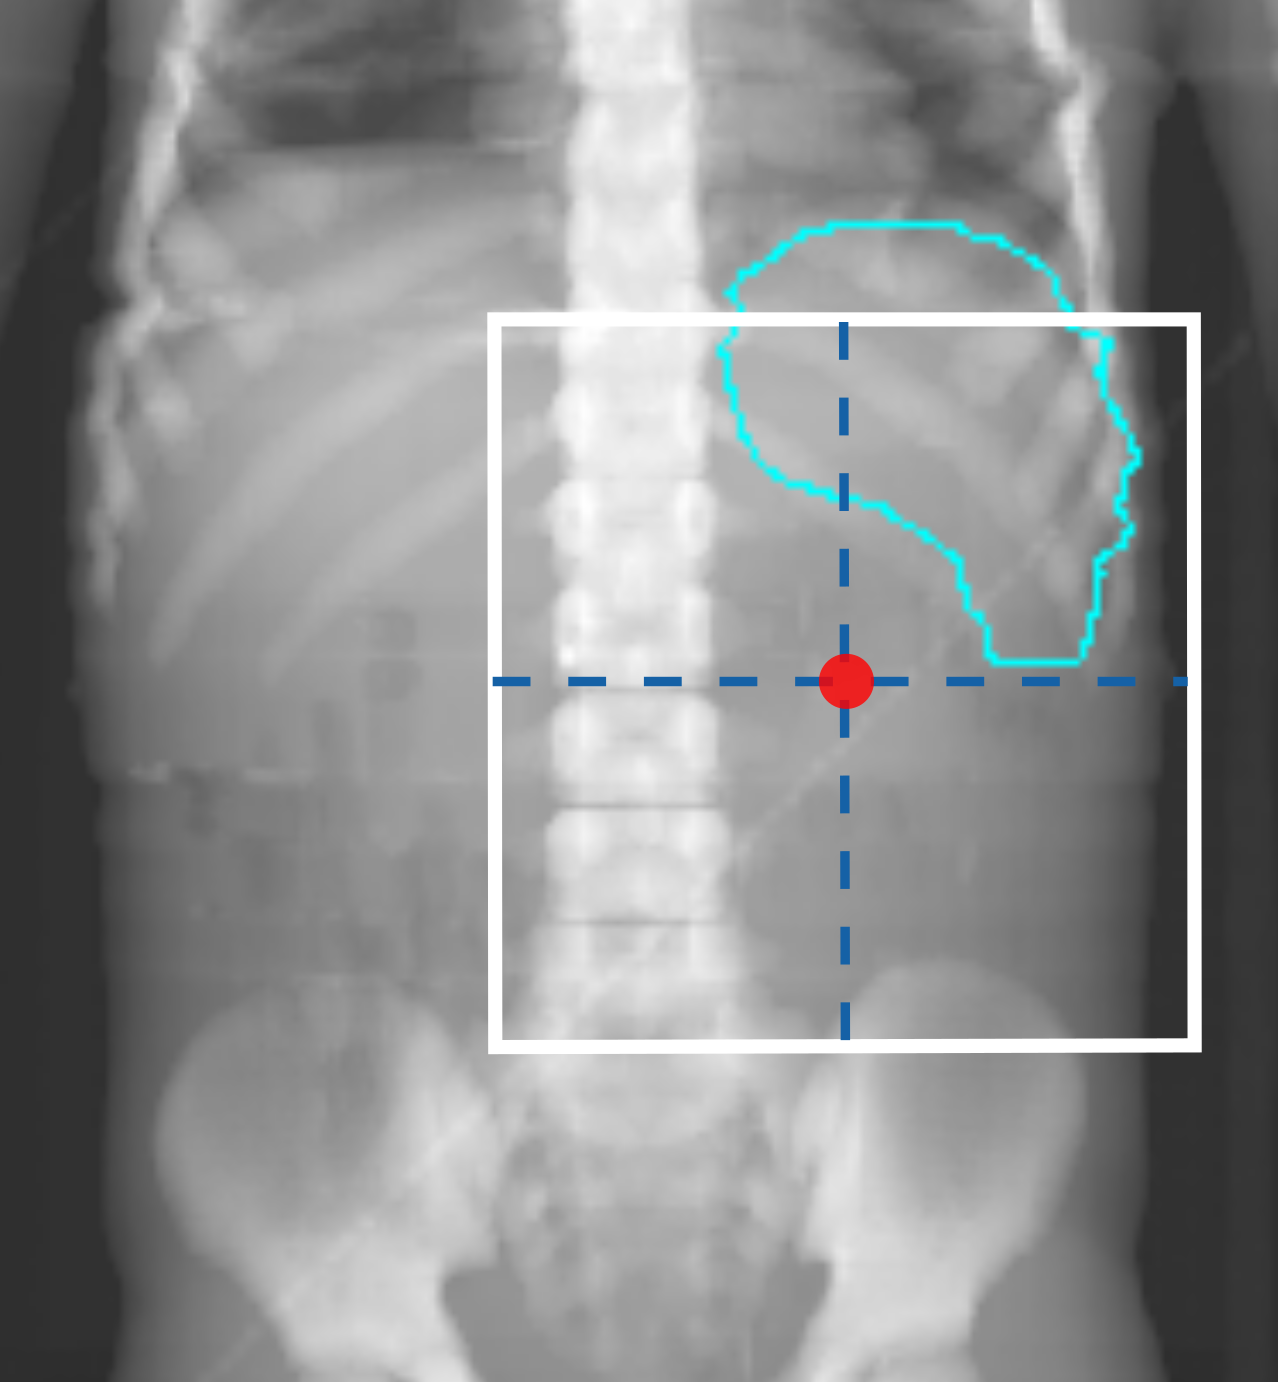

Figures 1(a) and 1(c) illustrate examples of actual historical plans on respective historical radiographs. As can be observed, a typical historical flank irradiation field is a rectangular area, with possible shielding blocks, that is located on the right or on the left flank. Irradiation is done by beams from anterior-posterior (AP) and posterior-anterior (PA) direction. Along right-left (RL), one field border is located at the edge of the patient’s body contour, while the other is located as to include the vertebral column (?). In some cases, blocks are placed to protect OARs from irradiation (Fig. 1(c)). In historical plans the isocenter is positioned in the center of the treatment field that is projected on the coronal plane (Fig. 1) and at the middle of the patient’s AP abdominal diameter.

To generate artificial plans, two reference digitally reconstructed radiographs (DRRs) were considered, randomly selected from the data. One DRR was derived from a CT of a 5-year old female patient without nephrectomy (ref 1 in Fig. 2), and the other was derived from a CT of a 4-year old female patient with nephrectomy of the left kidney (ref 2 in Fig. 2). Upon these two DRRs, boundaries defining the extent of variation for clinically reasonable fields were identified by an experienced pediatric radiation oncologist (B. V. Balgobind) Note that historical clinical guidelines are slightly different from current ones (e.g., currently the iliac crests should be safeguarded, unlike in Fig. 1(c)). Figure 2 shows two examples of landmark locations identifying possible plan variations, on the two reference DRRs. Specifically, given the boundaries of possible isocenter positions and field borders, plans with a rectangular field were generated by sampling uniformly within those boundaries.

For each plan generated, an additional version of that plan including one block was generated as well. A block was simulated as the area in the upper lateral corner enclosed by the border of the rectangular field and a line crossing two randomly sampled endpoints. The endpoints were sampled from two regions roughly covering the start and end points of rib 9 and rib 12 on the DRRs (regions indicated by the green boxes in Fig. 2). This way, a sampled block covered part of the liver (in right-sided plans) or part of the spleen (in left-sided plans). All plans consisted of two opposing and symmetrical beams in AP-PA directions irradiating one side of the abdominal flank. Figures 1(b) and 1(d) illustrate two examples of sampled artificial plans (without or with a block) on respective DRRs.

For some metrics and OARs, errors were relatively large for some of the clinical plans. This may be due to chance, because ten is a small number. For example, the large underestimation observed for the of the spleen for one clinical case (with and without block) is due to the ML-based approach wrongly predicting a value associated with a spleen that is located completely outside of the field. Another reason why errors were relatively large for the clinical plans is that the artificial plan generation method needs to be improved. Artificial plans were generated by sampling geometry properties uniformly within predefined boundaries on two reference DRRs. Uniform sampling might not be representative of the distribution clinical plans have. Moreover, we consulted a single radiation oncologist to define clinically acceptable boundaries to use in the sampling of artificial plans. Consulting multiple experts and allowing for a larger variation might better help covering the extent of variation that is present in historical plans (Sec. 2.2). For example, the isocenter locations of artificial left-sided plans were never sampled below the 1st lumbar vertebra (see Fig. 2) and approximately half of the values for the spleen in case of the artificial left-sided plans were close to the prescribed dose (14.4 Gy, see Fig. 5), which means that the spleen was often almost completely in-field in our artificially generated set of left-sided plans. When a block was applied, only a small part of the spleen was spared. However, in clinical practice, isocenter locations can be lower, and a larger part of the spleen might actually be outside the field (see Fig. 7). This might explain the relatively large errors observed in the two outlier cases in Figure 6 where the isocenter location of the clinical plans is lower than the sampled range. Ultimately, effort should be done to improve the sampling of artificial plans.